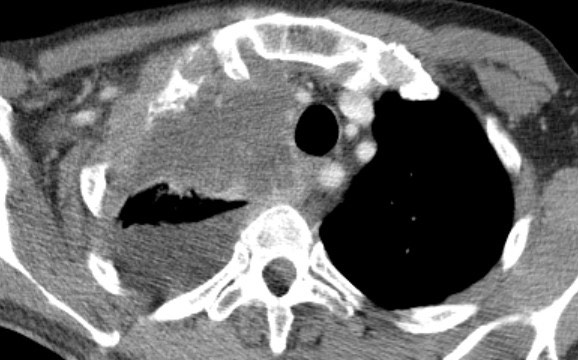

2850. В легком можно предположить